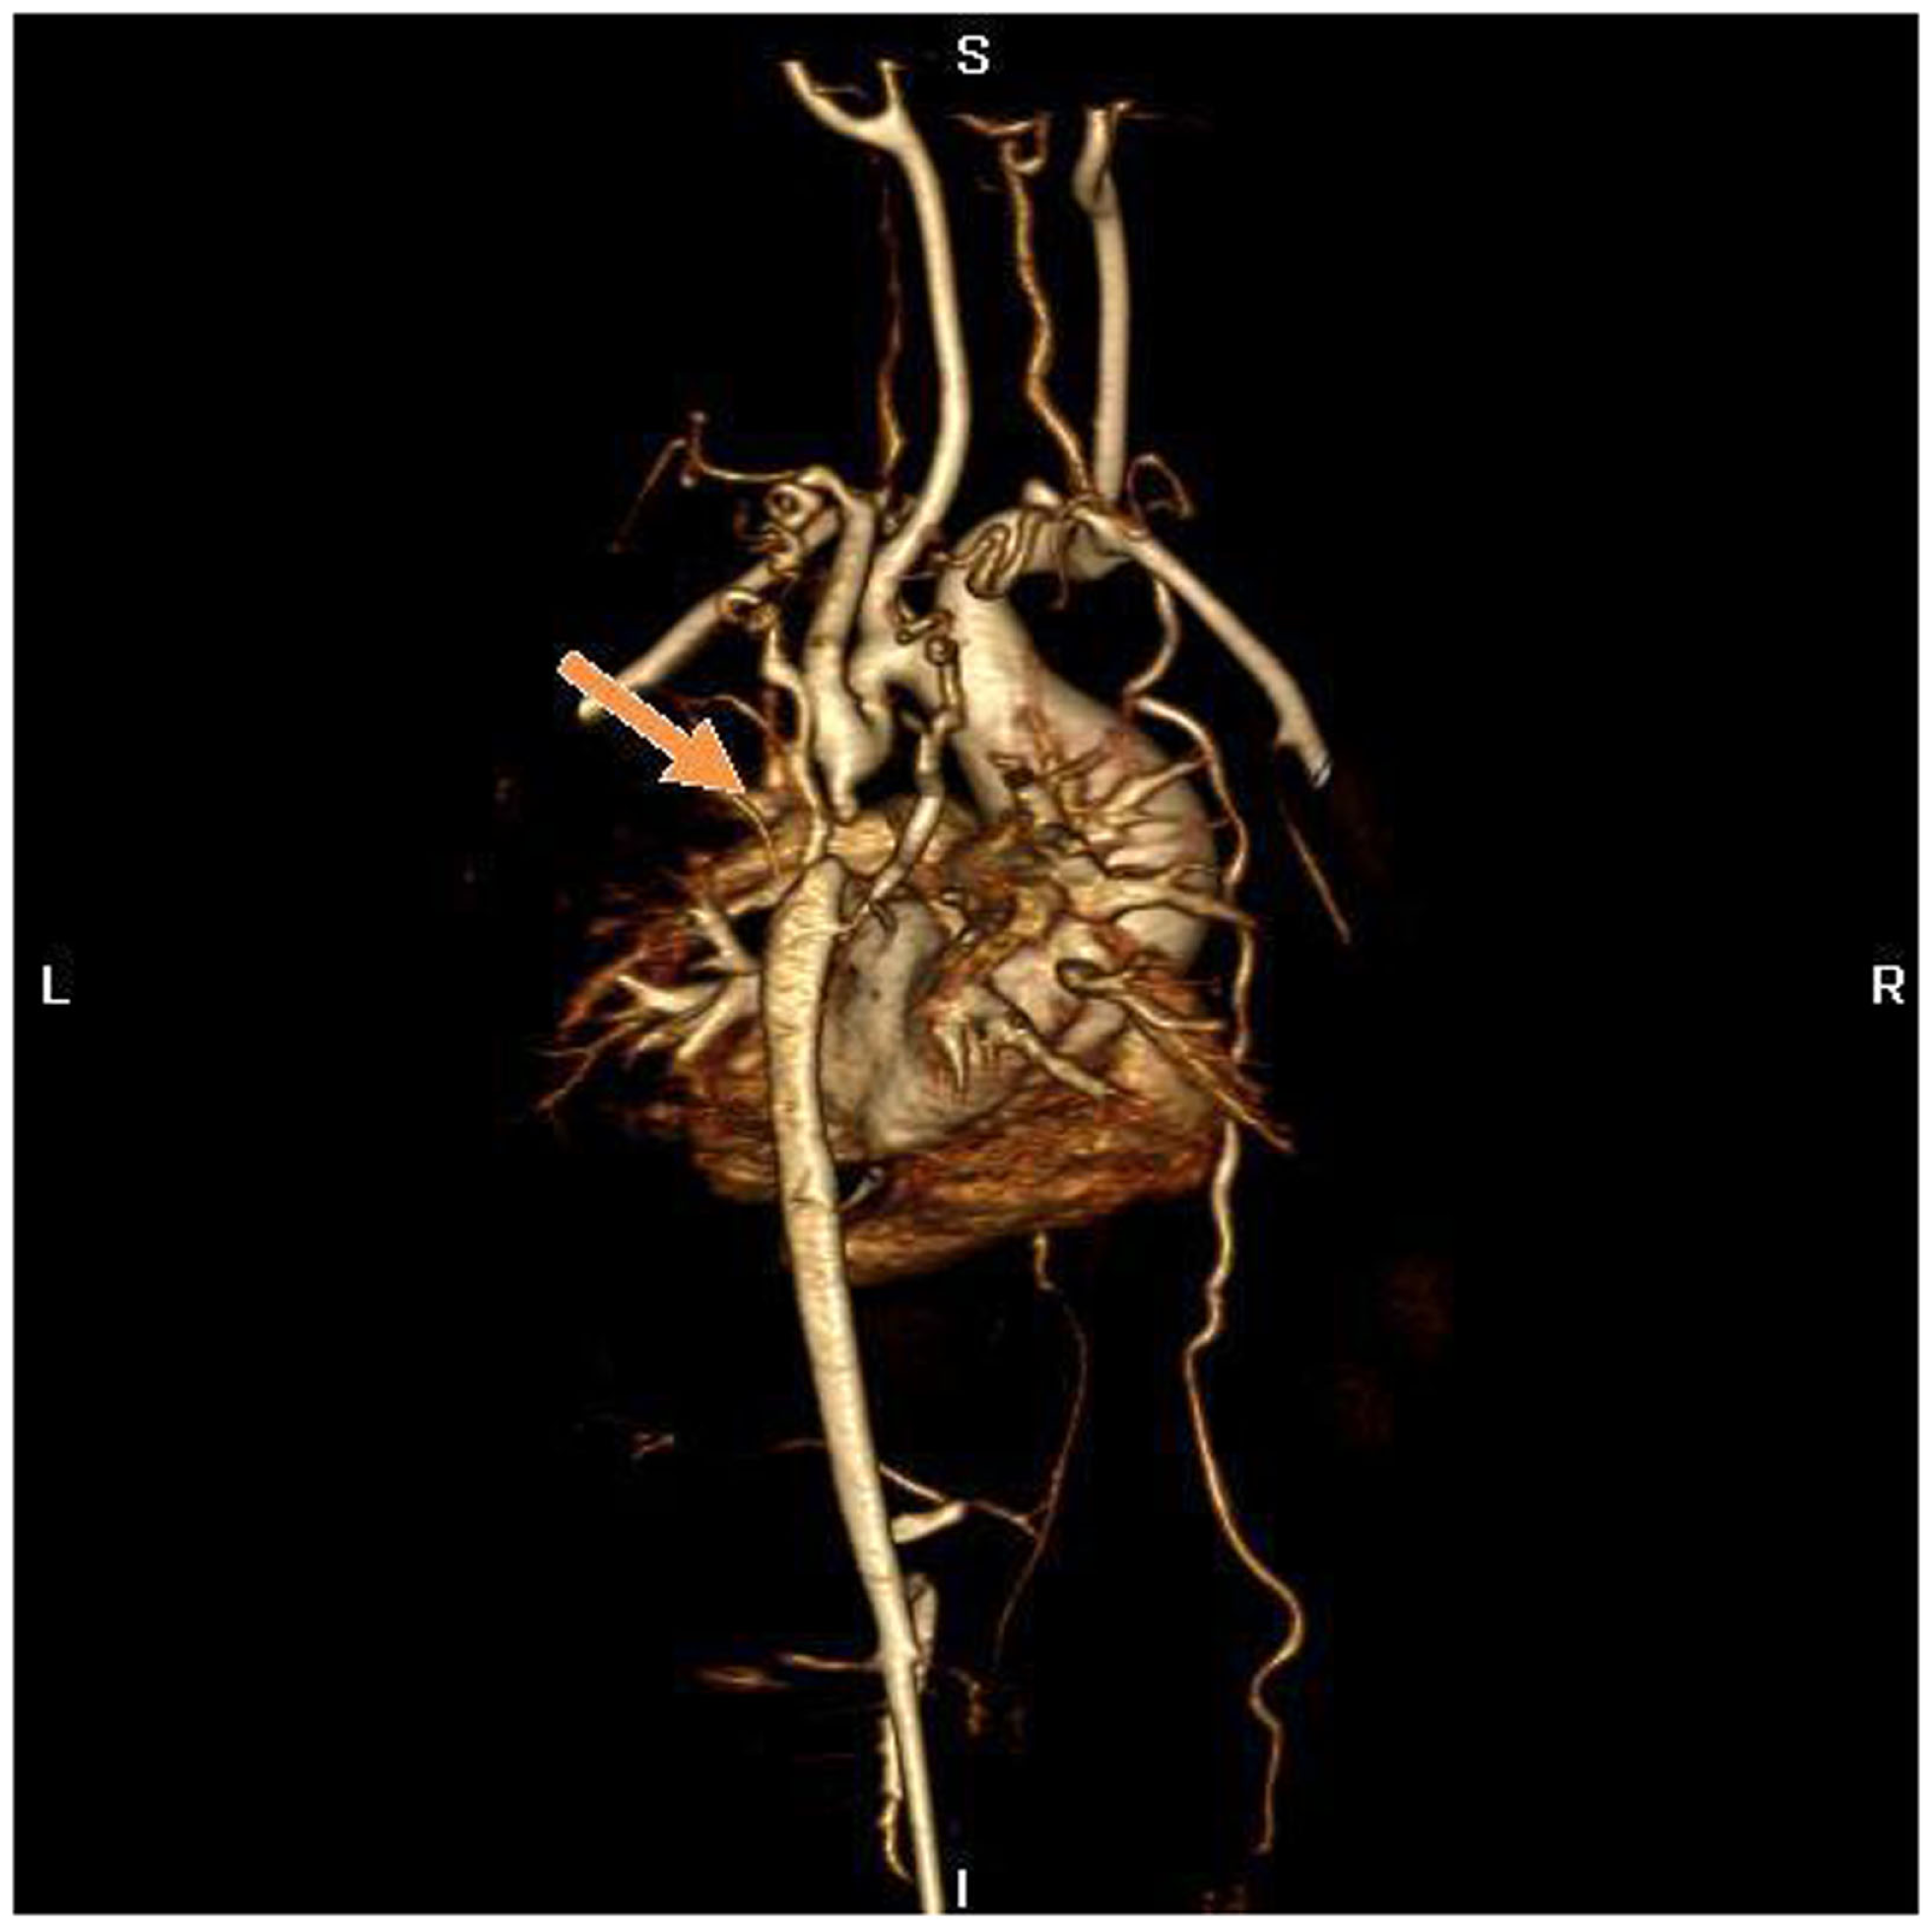

Figure 4

MR angiography, volume rendering 3D reconstruction. The arrow indicates the atretic aortic arch, diverticulums on either side of the zone of discontinuity suggests the presence of a fibrous strand at that position, compatible with the diagnosis of atresia. There are numerous collaterals such as both mammary arteries, intercostals arteries, and posterior mediastinal arteries. There was hypoplasia of the horizontal aorta and gothic aspect of the ascending aorta.